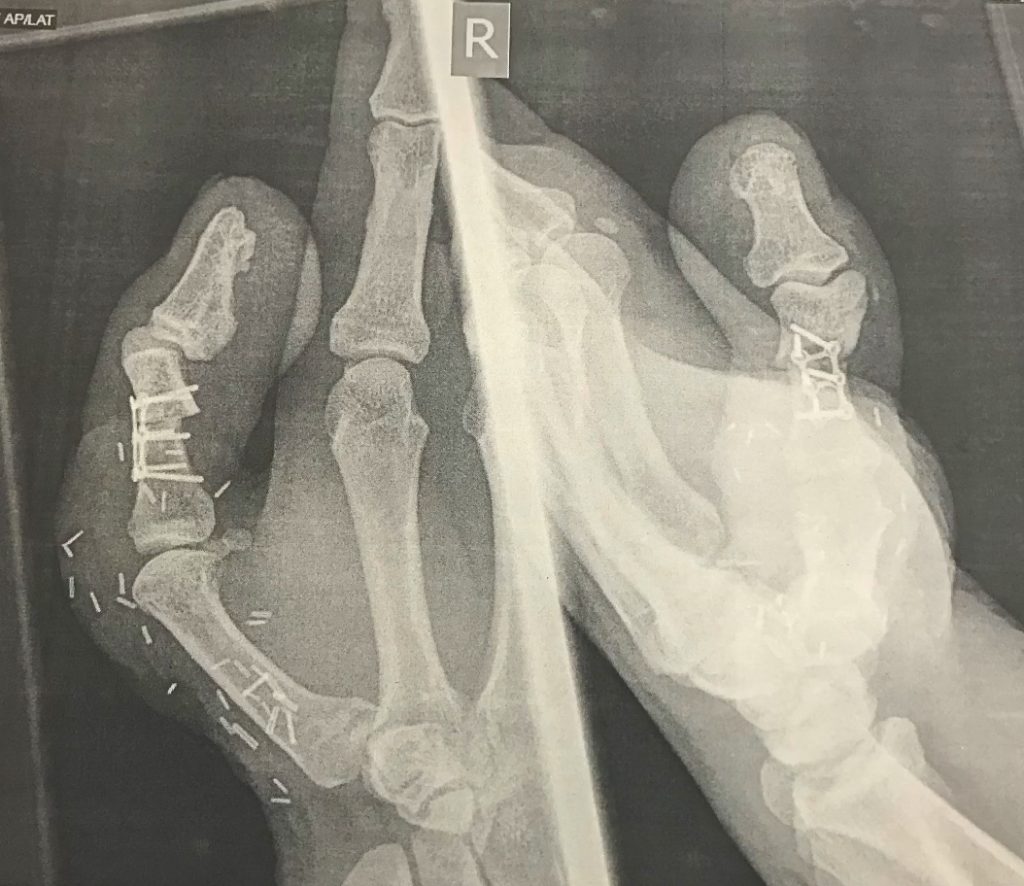

El 9 de enero de 2019, la mano derecha de David Lee quedó atrapada en un máquina que le trituró el dedo. Además del trauma de la pérdida de su dedo, el hombre temía no poder seguir ejerciendo su profesión, confección y arreglo de zapatos. La solución llegó de la mano del Hospital Universitario de Derby y Burton, lugar en el que hicieron efectivo un trasplante de su dedo gordo del pie a la mano

La operación, que duró diez horas fue acompañada de un largo proceso de recuperación, un año más tarde, David pudo retomar sus funciones normales en el trabajo.